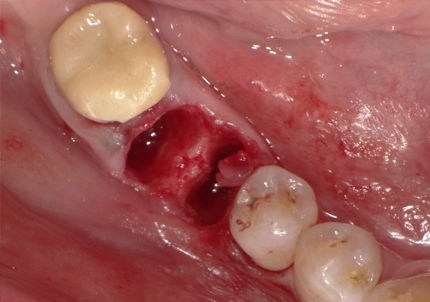

【左下ブリッジ5番6番歯根破折の為要抜歯】

【左下5番ソケットシールドテクニック】

【ソケットシールドテクニックにて頬側骨の形態を維持する (右の様な骨のへこみを作らない)】

【通常の抜歯により唇側骨(外側の骨)が吸収してへこんだ症例】

※ 通常、ソケットシールドテクニックは前歯部領域に用いるが小臼歯部でも採用しました

4.左下5番ソケットシールドテクニック

【ソケットシールドテクニックにより保存した歯牙片の内側にインプラントを埋入するCTシミュレーション】

【上記シミュレーションにて作製したガイドを用いたインプラント埋入】

5.インプラント埋入(2021年6月)

※ 初期固定35N/cm確認する